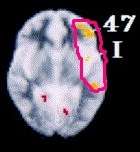

Меня вот например ещё интересует в каком поле по бродману дп/др локализируется и какую роль в этом всём может играть генетика.

Да-да видел, кстати в фмрт и ПЭТ исследованиях видна одна корреляция на счёт чрезмерной активации 47-го поля бродмана, правда я не знаю на что реагировали пациенты в ПЭТ исследовании.